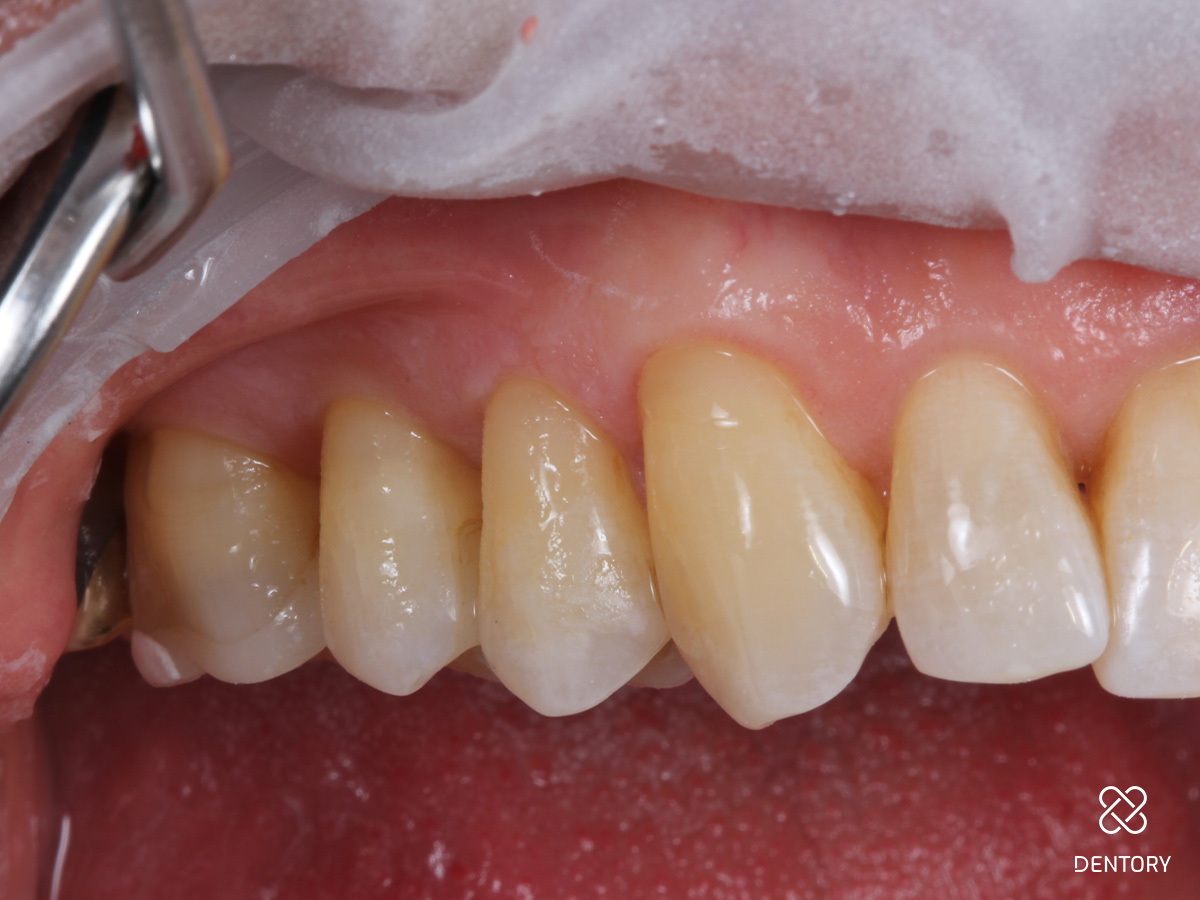

Abbildung 1

Ausgangssituation: Generalisierte Zahnhalsdefekte im Oberkiefer